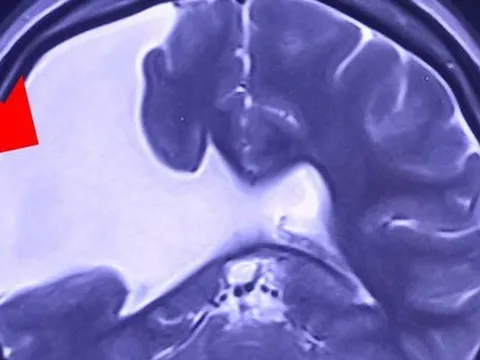

Nam thanh niên bị điện giật sống lại sau ba giờ ngừng tim

Nam thanh niên 20 tuổi bị điện giật, ngừng tim suốt 3 giờ đồng hồ, có nguy cơ mất não và suy đa tạng... được các bác sỹ cứu sống.